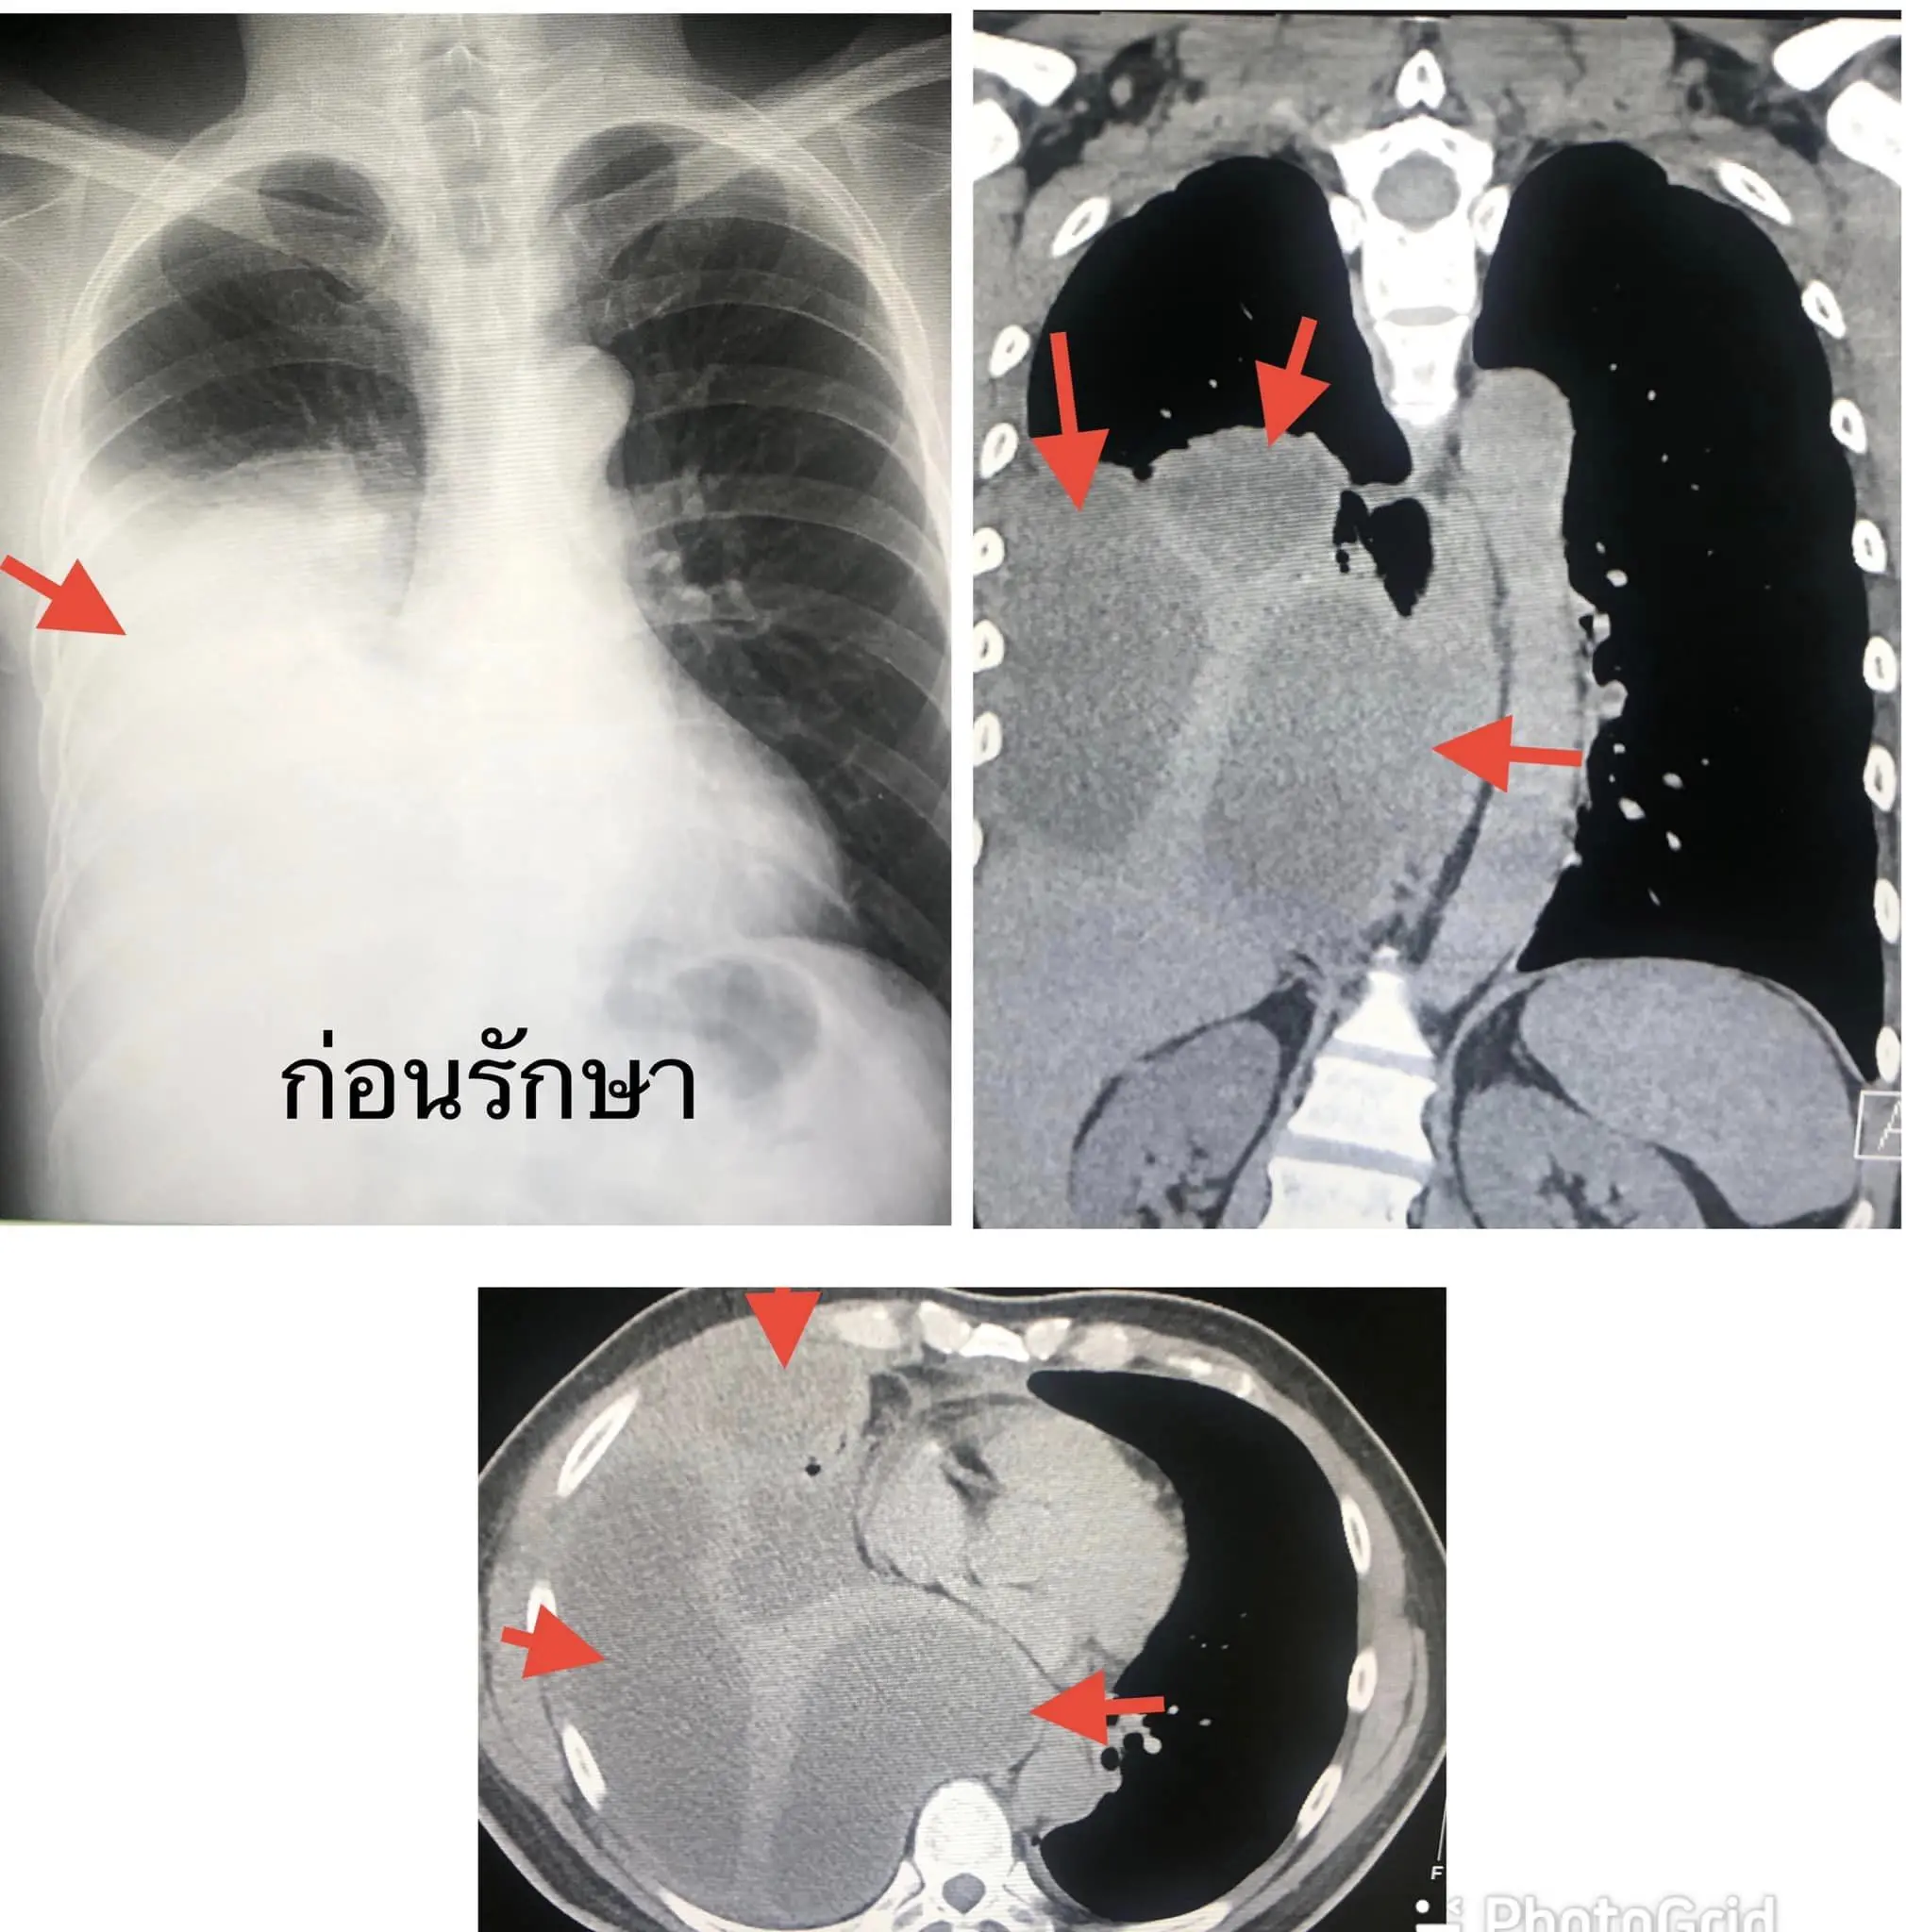

ทุกคนต้องดูแลสุขภาพช่องปากและฟันให้ดี อย่าปล่อยให้ฟันผุ มีการติดเชื้อในรากฟัน อาจส่งผลให้เกิดหนองในช่องเยื่อหุ้มปอด (Empyema Thoracis) ผู้ป่วยชายอายุ 53 ปี มาโรงพยาบาลด้วยอาการไอ เสมหะสีเขียวๆ เจ็บที่หน้าอกข้างขวาเวลาไอและมีไข้ 1 สัปดาห์ ไม่ปวดฟัน ไม่เจ็บเหงือก ไม่มีโรคประจำตัว ไม่กินเหล้า ไม่สูบบุหรี่ตรวจร่างกาย มีไข้ต่ำๆ ฟังปอดข้างขวาได้ยินเสียงลดลง เจาะเลือด พบเม็ดเลือดขาวในเลือดสูง 16,030

เอกซเรย์ปอดเห็นน้ำในปอดข้างขวา ทำคอมพิวเตอร์ปอดเห็นก้อนน้ำหลายก้อนเกาะอยู่ในช่องเยื่อหุ้มปอดข้างขวา(ดูรูป)ใส่สายระบายน้ำผ่านทางผิวหนังเข้าเยื่อหุ้มปอดข้างขวา 2 ตำแหน่ง ได้หนองสีเหลืองขุ่น มีกลิ่นเหม็น 1,200 ซีซี (ดูรูป) ย้อมเชื้อพบแบคทีเรียทั้งกรัมบวกและกรัมลบ (gram negative bacilli, gram positive cocci in pairs and chains, gram positive bacilli)ให้ยาปฏิชีวนะทางเส้นเลือดครอบคลุมทั้งเชื้อแบคทีเรียที่ต้องการและไม่ต้องการออกซิเจนเพาะเชื้อแบคทีเรียขึ้น Streptococcus constellatus คงมีอีกหลายเชื้อ

แต่เพาะไม่ขึ้นปรึกษาทันตแพทย์ เอกซเรย์พบฝีหนองที่รากฟัน (dental root abscess) ต้องถอนฟันทั้งหมด 9 ซี่ ทั้งๆที่ก่อนหน้านี้ ผู้ป่วยไม่รู้สึกปวดฟันใดๆหลังให้ยาปฏิชีวนะทางเส้นเลือด 1 สัปดาห์ อาการดีขึ้น เอกซเรย์ปอดดีขึ้น